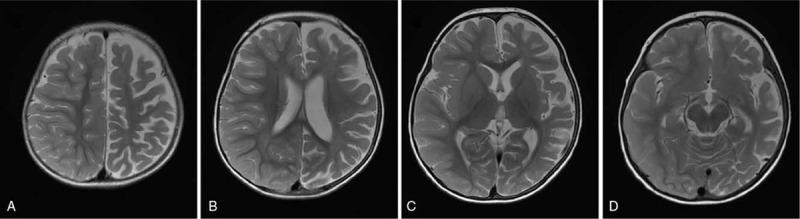

Acute encephalopathy with biphasic seizures and late reduced diffusion (AESD) is a condition characterized by biphasic convulsions and disturbance of consciousness. In Japan, the most common pediatric cases of acute encephalopathy are associated with infection. AESD usually occurs in early childhood, with the characteristic magnetic resonance imaging (MRI) appearance called "bright tree appearance." The disease often has neurological sequelae and interferes with the schooling of children and their activities of daily living; however, there are few clinical case reports of hemiplegia caused by AESD.

急性脑病伴双相抽搐和后期弥散受限(AESD)是一种以双相抽搐和意识障碍为特征的疾病。在日本,最常见的小儿急性脑病与感染有关。AESD 通常发生在幼儿期,具有称为“亮树征”的特征性磁共振成像(MRI)表现。该疾病常伴有神经后遗症,影响儿童的学业和日常生活活动;然而,AESD 引起偏瘫的临床病例报告很少。